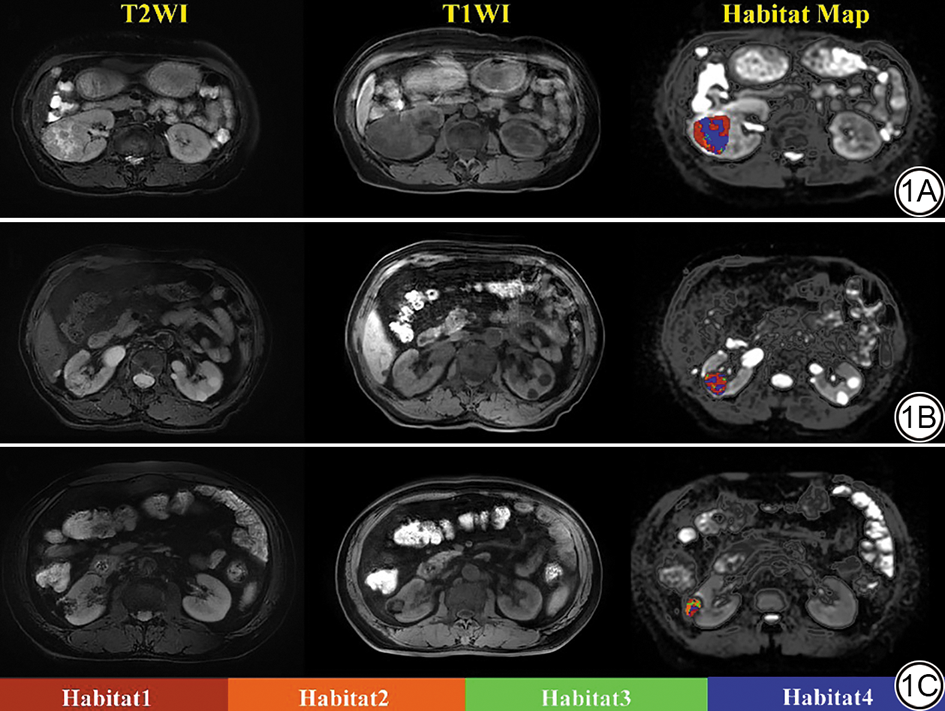

影像学分析由一名对病理结果不知情的放射科主治医师完成(具有>5年的肾脏影像学经验)。参考T2WI图像,在DWI图像(b值=1000 s/mm2)上逐层手动勾画感兴趣区(region of interest, ROI),并参考其他MRI序列(图1),这些ROI最终构成感兴趣体积(volume of interest, VOI)。最终的VOI由具有10年以上经验的第二位放射科副主任医师验证。然后将VOI传播到相应的参数图,包括D、μ、β、MD、MK、Dt、D*、f和ADC图。最后,得到各VOI在不同参数下的均值,进一步分析。

图1  感兴趣区(ROI)勾画示意图。1A:男,66岁,右肾高级别透明透明细胞癌(Fuhrman Ⅳ级),病灶在T2WI上呈混杂高信号,T1WI呈低信号,Habitat Map为相应的生境图像;1B:女,49岁,右肾低级别透明细胞癌(Fuhrman Ⅱ级),病灶在T2WI上呈稍高信号,T1WI呈稍低信号,Habitat Map为相应的生境图像;1C:女,74岁,右肾乏脂血管平滑肌脂肪瘤,病灶在T2WI上呈稍高信号,T1WI呈稍低信号,Habitat Map为相应的生境图像。

Fig. 1  Region of interest (ROI) delineation schematic diagram. 1A: Male, 66-year-old, patient with high-grade clear cell renal cell carcinoma (Fuhrman grade Ⅳ) in the right kidney, the lesion exhibits heterogeneous hyperintensity on T2-weighted imaging and hypointensity on T1-weighted imaging; the Habitat Map represents the corresponding habitat imaging. 1B: Female, 49-year-old, patient with low-grade clear cell renal cell carcinoma (Fuhrman grade Ⅱ) in the right kidney, the lesion appears mildly hyperintense on T2-weighted imaging and mildly hypointense on T1-weighted imaging; the Habitat Map represents the corresponding habitat imaging. 1C: Female, 74-year-old, patient with a fat-poor angiomyolipoma in the right kidney, the lesion shows mildly hyperintense signal on T2-weighted imaging and mildly hypointense signal on T1-weighted imaging; the Habitat Map represents the corresponding habitat imaging.